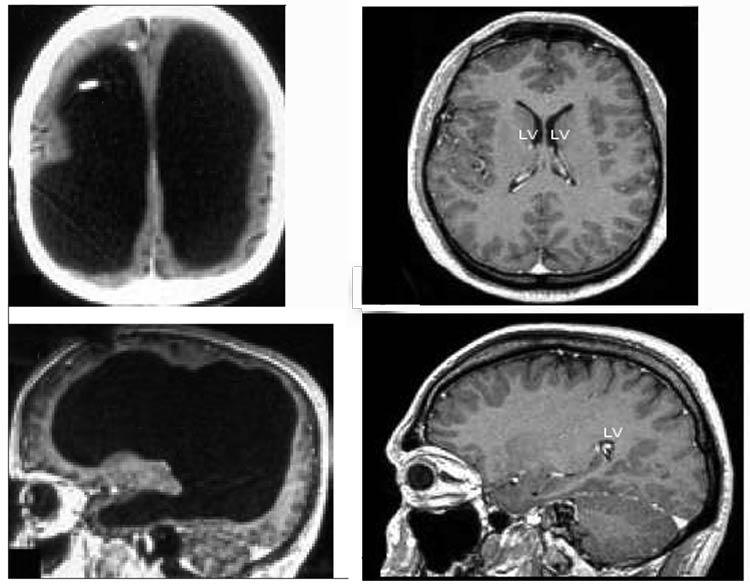

On the left is the scan of this man's brain, while on the right is what a normal brain looks like.

No, I'm not insulting anyone. This has really shown up in a medical study. This guy has a tiny brain. In fact, doctors estimate he's had a 50-75% reduction in brain volume, which has been replaced with fluid.

Apparently he had a shunt inserted when he was 14 to reduce a condition known as hydrocephalus, or "water on the brain." Once that shunt was removed, for whatever reason, the tiny chambers that hold cerebrospinal fluid (which cushions the brain) underwent massive expansion over the many years until it reached his condition today.

He has lived an entirely normal life and is now 44 years old. There were no outward signs of this condition, and it was only discovered during an examination that started because of mild weakness in one of his legs.

Astounding, no? Doctors are saying this is a prime example of brain plasticity, where the brain adapts to damage by adjusting different parts of itself to handle various functions that it wasn't originally intended to do.